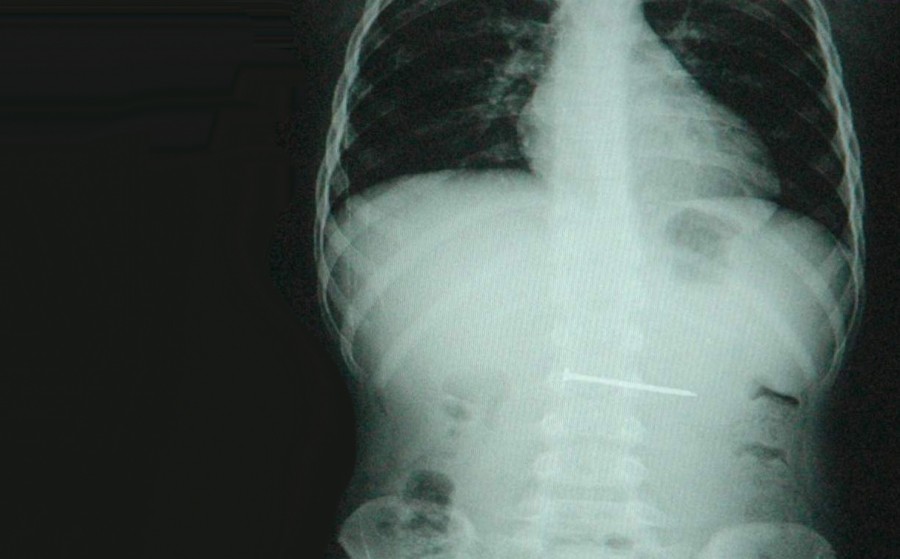

Olay, Konya’nın Altınekin ilçesine bağlı Yenikuyu köyünde meydana geldi. Edinilen bilgiye göre, ilköğretim 3. sınıf öğrencisi Tunahan Kavaşçınar (8), evlerindeki televizyonda çizgi film izlediği sırada ağzına götürdüğü 8 santimetre uzunluğundaki çiviyi yuttu. Çiviyi yuttuğunu fark eden çocuk, hemen durumu annesine anlattı. Telaşlanan yakınları hemen çocuğu alarak Konya Farabi Hastanesi’ne götürdü. Hastanede filmi çekilen çocuğun yuttuğu çivinin midesinde olduğu tespit edildi. Bunun üzerine Genel Cerrahi Uzmanı Op. Dr. Bülent Erenoğlu, endoskopi yöntemiyle midedeki çiviyi çıkarmayı başardı.

Hastanın durumuyla ilgili bilgi veren Doktor Erenoğlu, “Endoskopi yöntemiyle çıkarttığımız için durumu çok iyi. Mideyi yırtmış olsaydı, ameliyatla çıkarmak zorunda kalırdık. Erken müdahale olduğu için meydana gelebilecek kötü bir olayı atlatmış olduk” dedi. Televizyonda çizgi film izlerken çiviyi yuttuğunu belirten Tunahan Kavaşçınar ise,”Hemen anneme söyledim. Sonra doktora geldik. Çiviyi çıkarttılar, birazcık korktum” şeklinde konuştu.